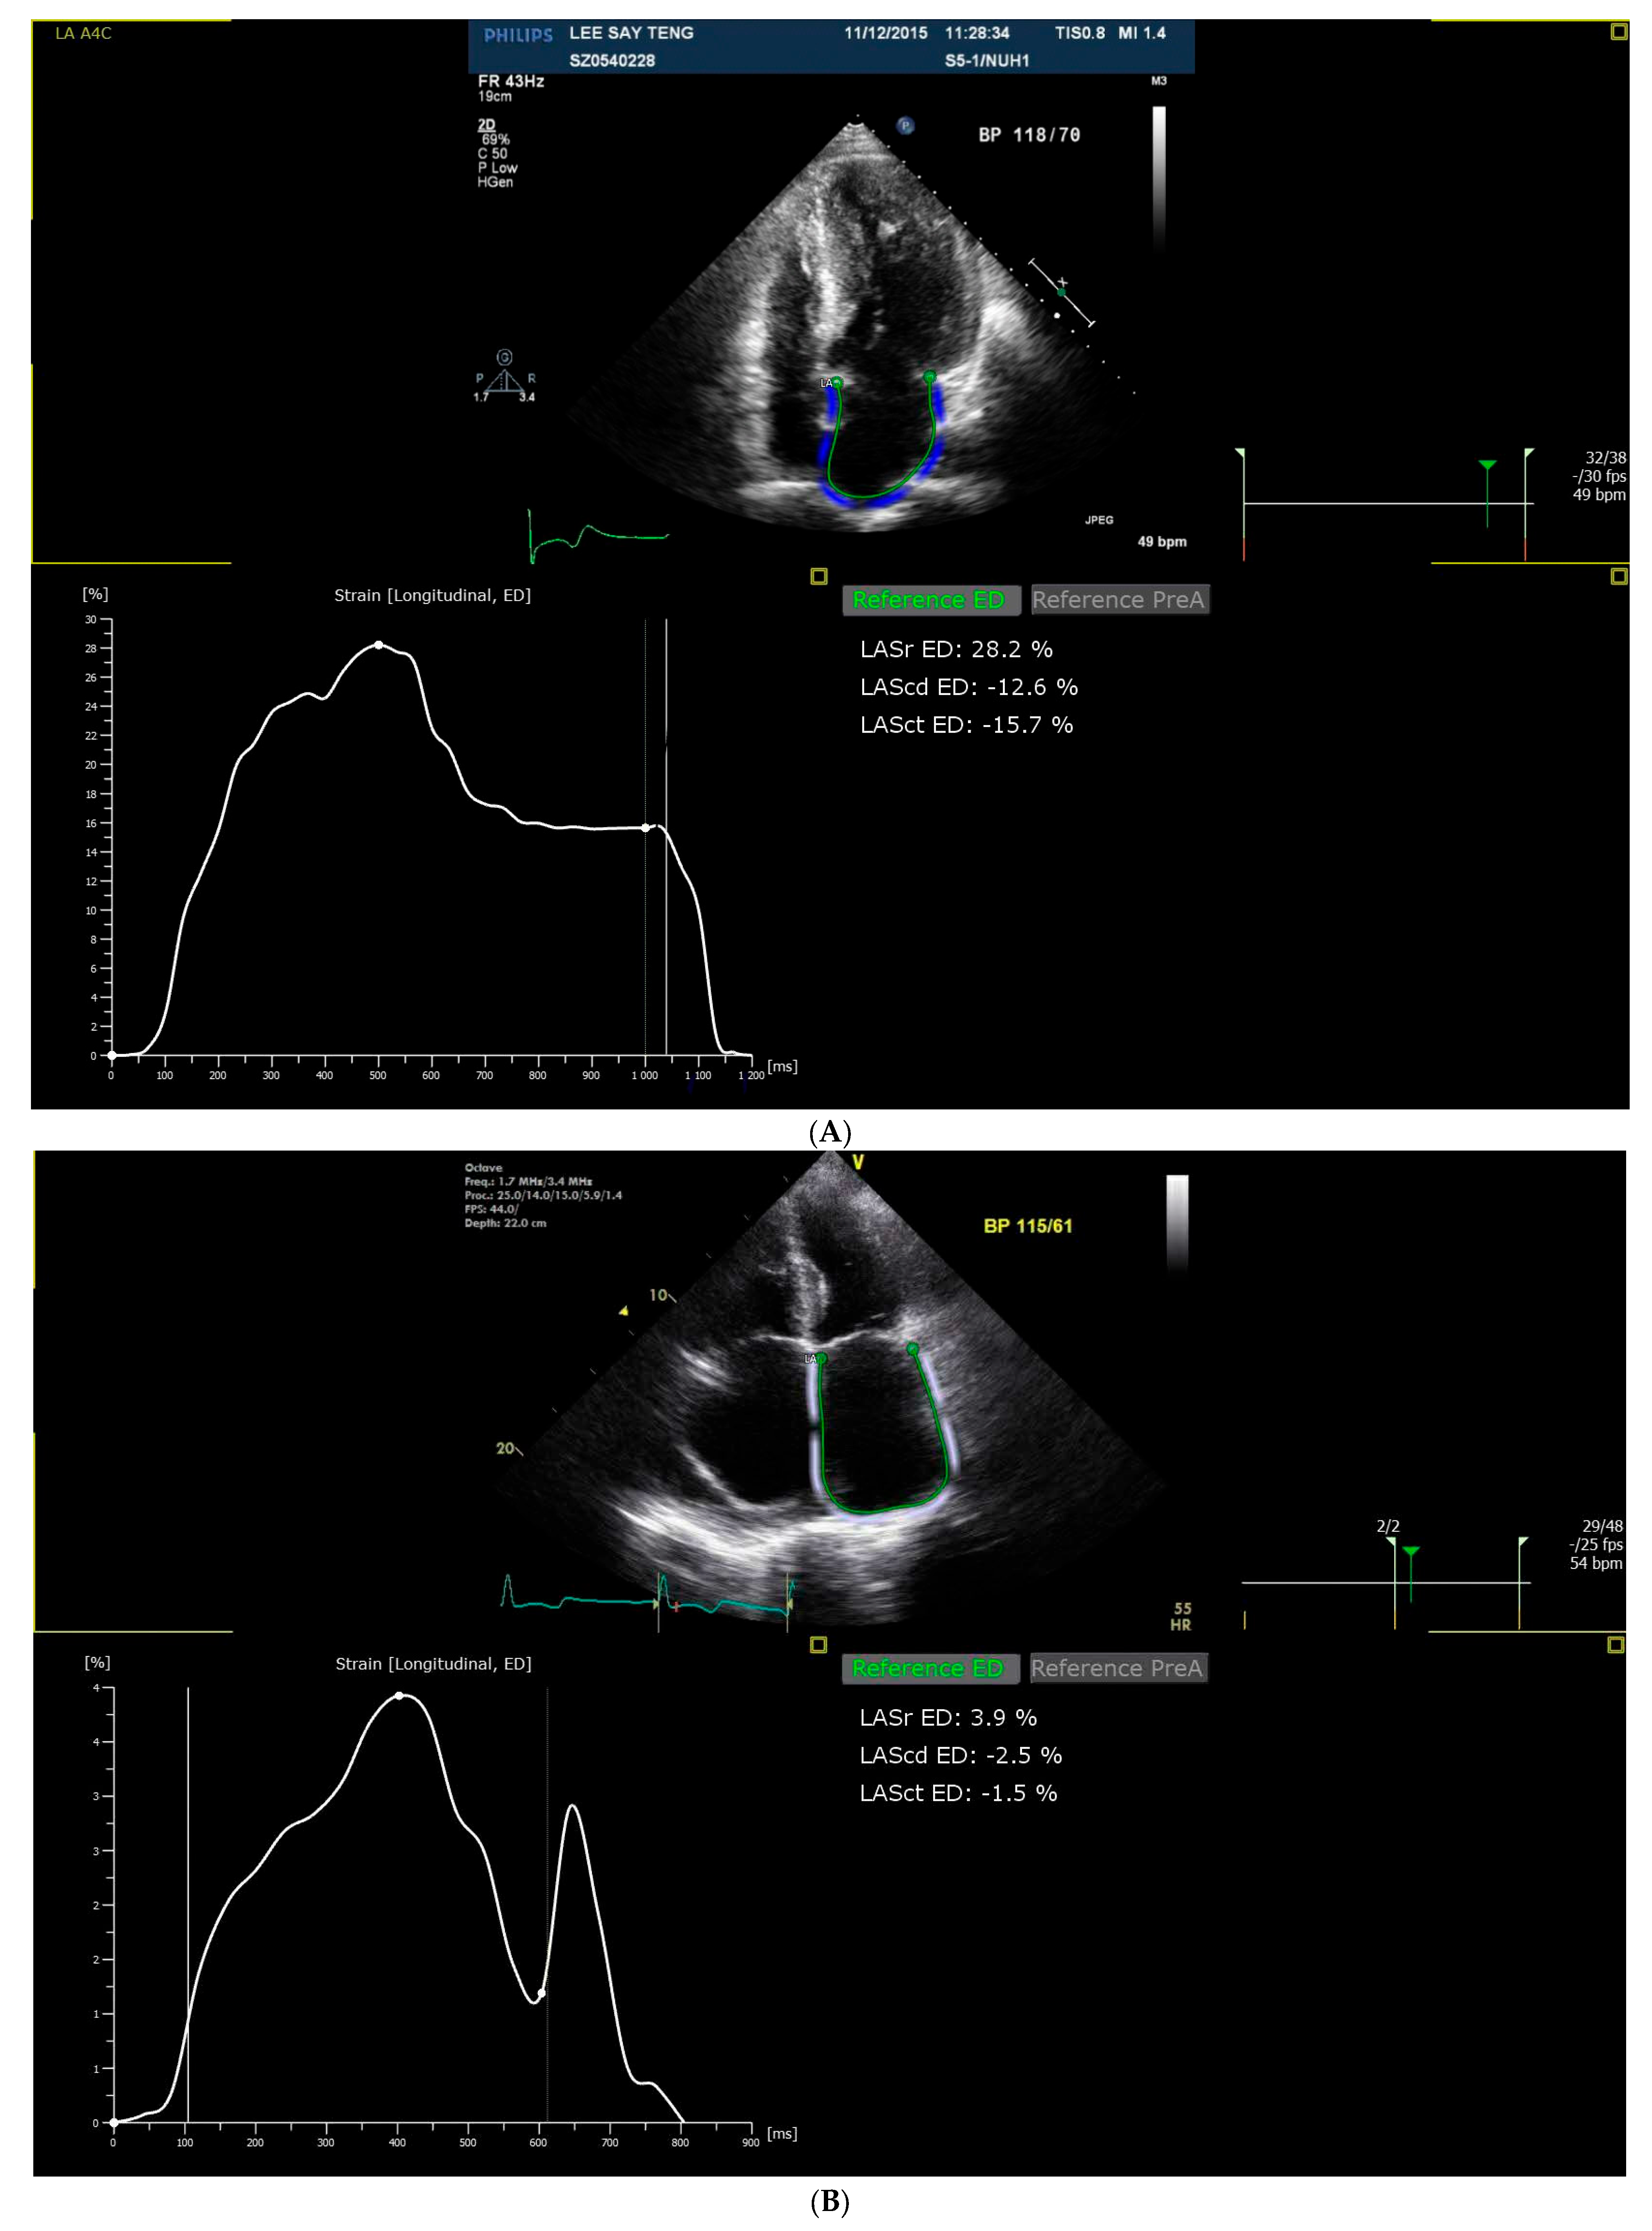

2.4. Strain Analysis

| LASr | Left atrial reservoir strain |

| LAScd | Left atrial conduit strain |

| LASct | Left atrial contraction strain |